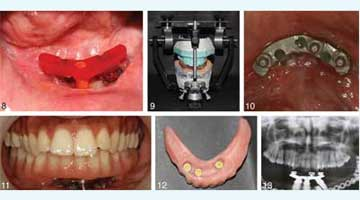

Mini dental implants in stabilizing a loose lower denture

June 13, 2012

Denture conversion: a step-by-step protocol

March 6, 2012